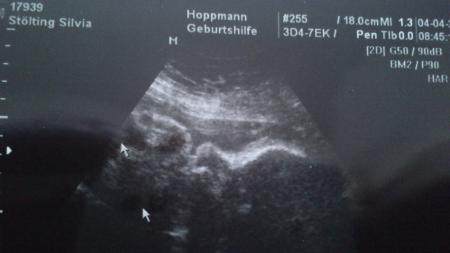

Hallo ihr lieben Bin wieder wieder da von der VU :-) Baby gehts super wiegt jetzt 2800 g und ist 45 cm groß laut us bin ich eine Woche weiter zwerg hat die entwicklung von der 35.SSW Ändern darf er den ET ja nun nicht mehr sagte aber solle damit rechnen das der kleine schon eine Woche früher kommen kann :-)) Mein gewicht hat sich was getan bin nur noch ausgangsgewicht -8 Kg hab endlich mal 1 KG zu genommen :-)) Alle anderen werte waren auch gut Blut wurde noch abgenommen sollte ich bis morgen nachmittag nichts hören von meinem FA sind die werte alle in Ordnung. Ich freu mich so

Bild zu